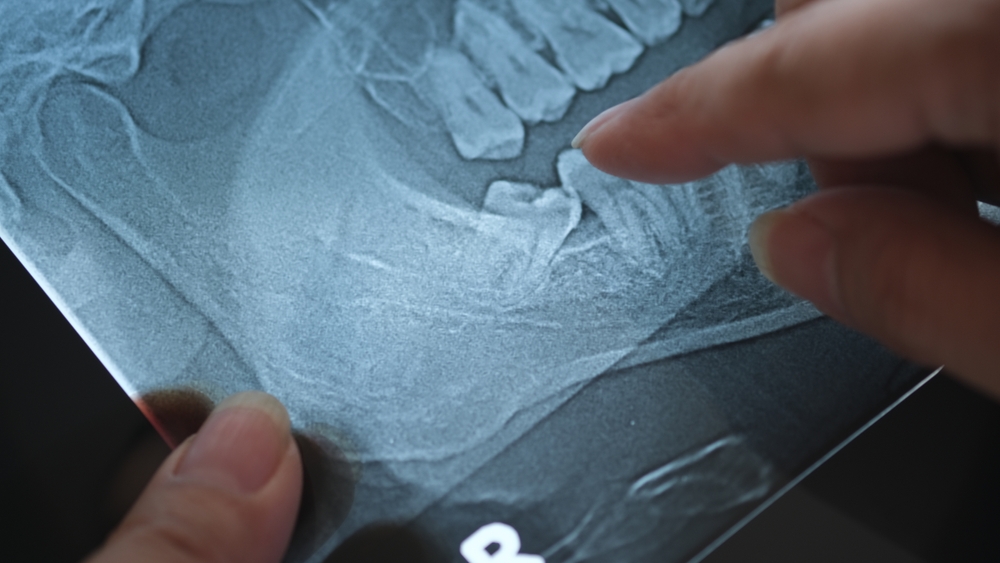

Wisdom Tooth Extraction Vista

If your wisdom teeth are impacted, it is recommended that you remove them. But keep in mind that failing to remove teeth that are growing in at an angle can cause them to be trapped within your jawbone, resulting in pain and a myriad of complications that may require additional treatment. Before extracting the teeth, …